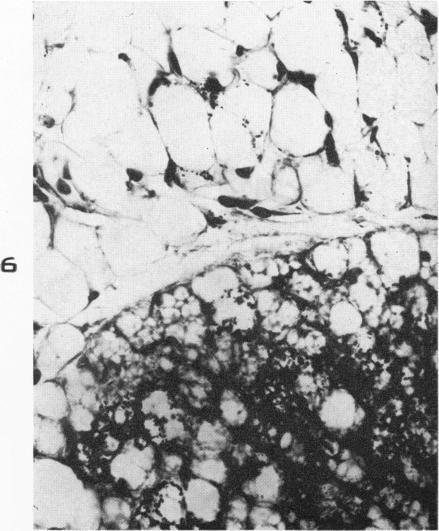

ARONSON S M, SHWARTZMAN G

Am J Pathol. 1956 Mar-Apr;32(2):315-33.